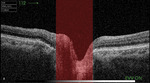

Rycina 1B. Grubość włókien nerwowych nerwu wzrokowego z ryciny 1A reprezentuje czarna pofalowana linia

Zdrowy człowiek posiada niewielkie zagłębienie w środku tarczy nerwu wzrokowego (wnęka naczyniowa) pozwalające dostać się żyle i tętnicy środkowej siatkówki do oka. Stosunek średnicy tarczy nerwu wzrokowego do zagłębienia, oznaczany skrótem c/d (cup – zagłębienie/disc – tarcza nerwu wzrokowego), wynosi najczęściej 0,3-0,4 (ryc. 1A-B). Utrata włókien nerwowych powoduje poszerzanie się zagłębienia nerwu wzrokowego (ryc. 2A-C) aż do momentu, gdy średnica tarczy jest prawie równa średnicy zagłębienia (c/d = 0,9) – mówimy wtedy o jaskrze prawie dokonanej. W tym przypadku ostrość wzroku określa się jako poczucie światła, z reguły po stronie skroniowej chorego oka. Jaskra dokonana oznacza natomiast całkowitą utratę widzenia, czyli brak poczucia światła.

Rycina 2B. Grubość włókien nerwowych nerwu wzrokowego z ryciny 2A reprezentuje czarna pofalowana linia